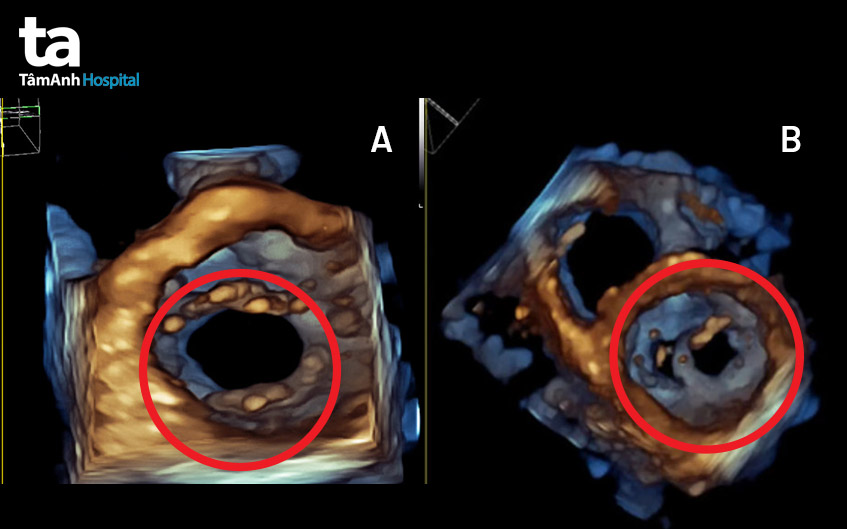

Ông Phạm Khoa (52 tuổi, quận 1, TP HCM) khám sức khỏe tại Bệnh viện Đa khoa Tâm Anh, bác sĩ tim mạch nghe tim có âm thổi nhẹ, kết quả siêu âm tim 4D phát hiện van 2 lá của bệnh nhân có 2 lỗ. Đây là bệnh lý tim bẩm sinh hiếm gặp.

BS.CKI Vũ Năng Phúc, Trưởng khoa Tim bẩm sinh BVĐK Tâm Anh TP HCM cho biết, van hai lá 2 lỗ không hẹp và hở van chỉ ở mức độ trung bình (2,5/4) nên ông Khoa không cần phẫu thuật. Ông được điều trị bằng thuốc, bác sĩ theo dõi chặt chẽ, phòng bệnh tiến triển nặng thêm.

“Thông thường, hở van tim ở mức độ từ nhẹ đến trung bình sẽ không gây ra triệu chứng rõ rệt. Như trường hợp bệnh nhân Khoa, suốt nhiều năm liền không biết mình mắc bệnh. Nếu trong quá trình khám, bác sĩ không tinh ý khi nghe tiếng thổi ở tim và chỉ định siêu âm tim sẽ không phát hiện bệnh. Đồng thời, kỹ thuật siêu âm tim 4 chiều qua thành ngực với độ phân giải cao được áp dụng tại BV Tâm Anh giúp phát hiện bất thường này dễ dàng”, bác sĩ Phúc nói.